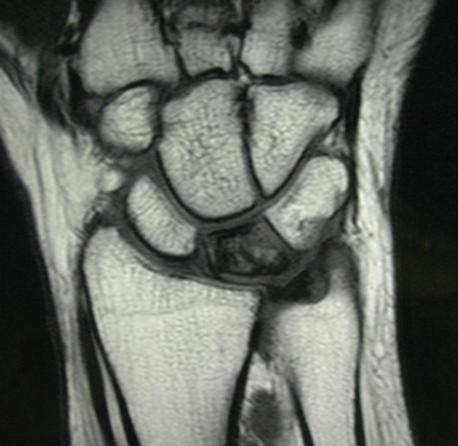

Третья стадия характеризуется уменьшением размеров лучезапястной кости, ее распадом на отдельные фрагменты и миграцией этих частиц. Симптомы болезни Кинбека становятся более выраженными, боли усиливаются. Изменения хорошо визуализируются с помощью рентгенографии или магнитно-резонансной томографии. На снимках отчетливо видны патологии полулунной кости, неровности контуров и начальные признаки распада на фрагменты.